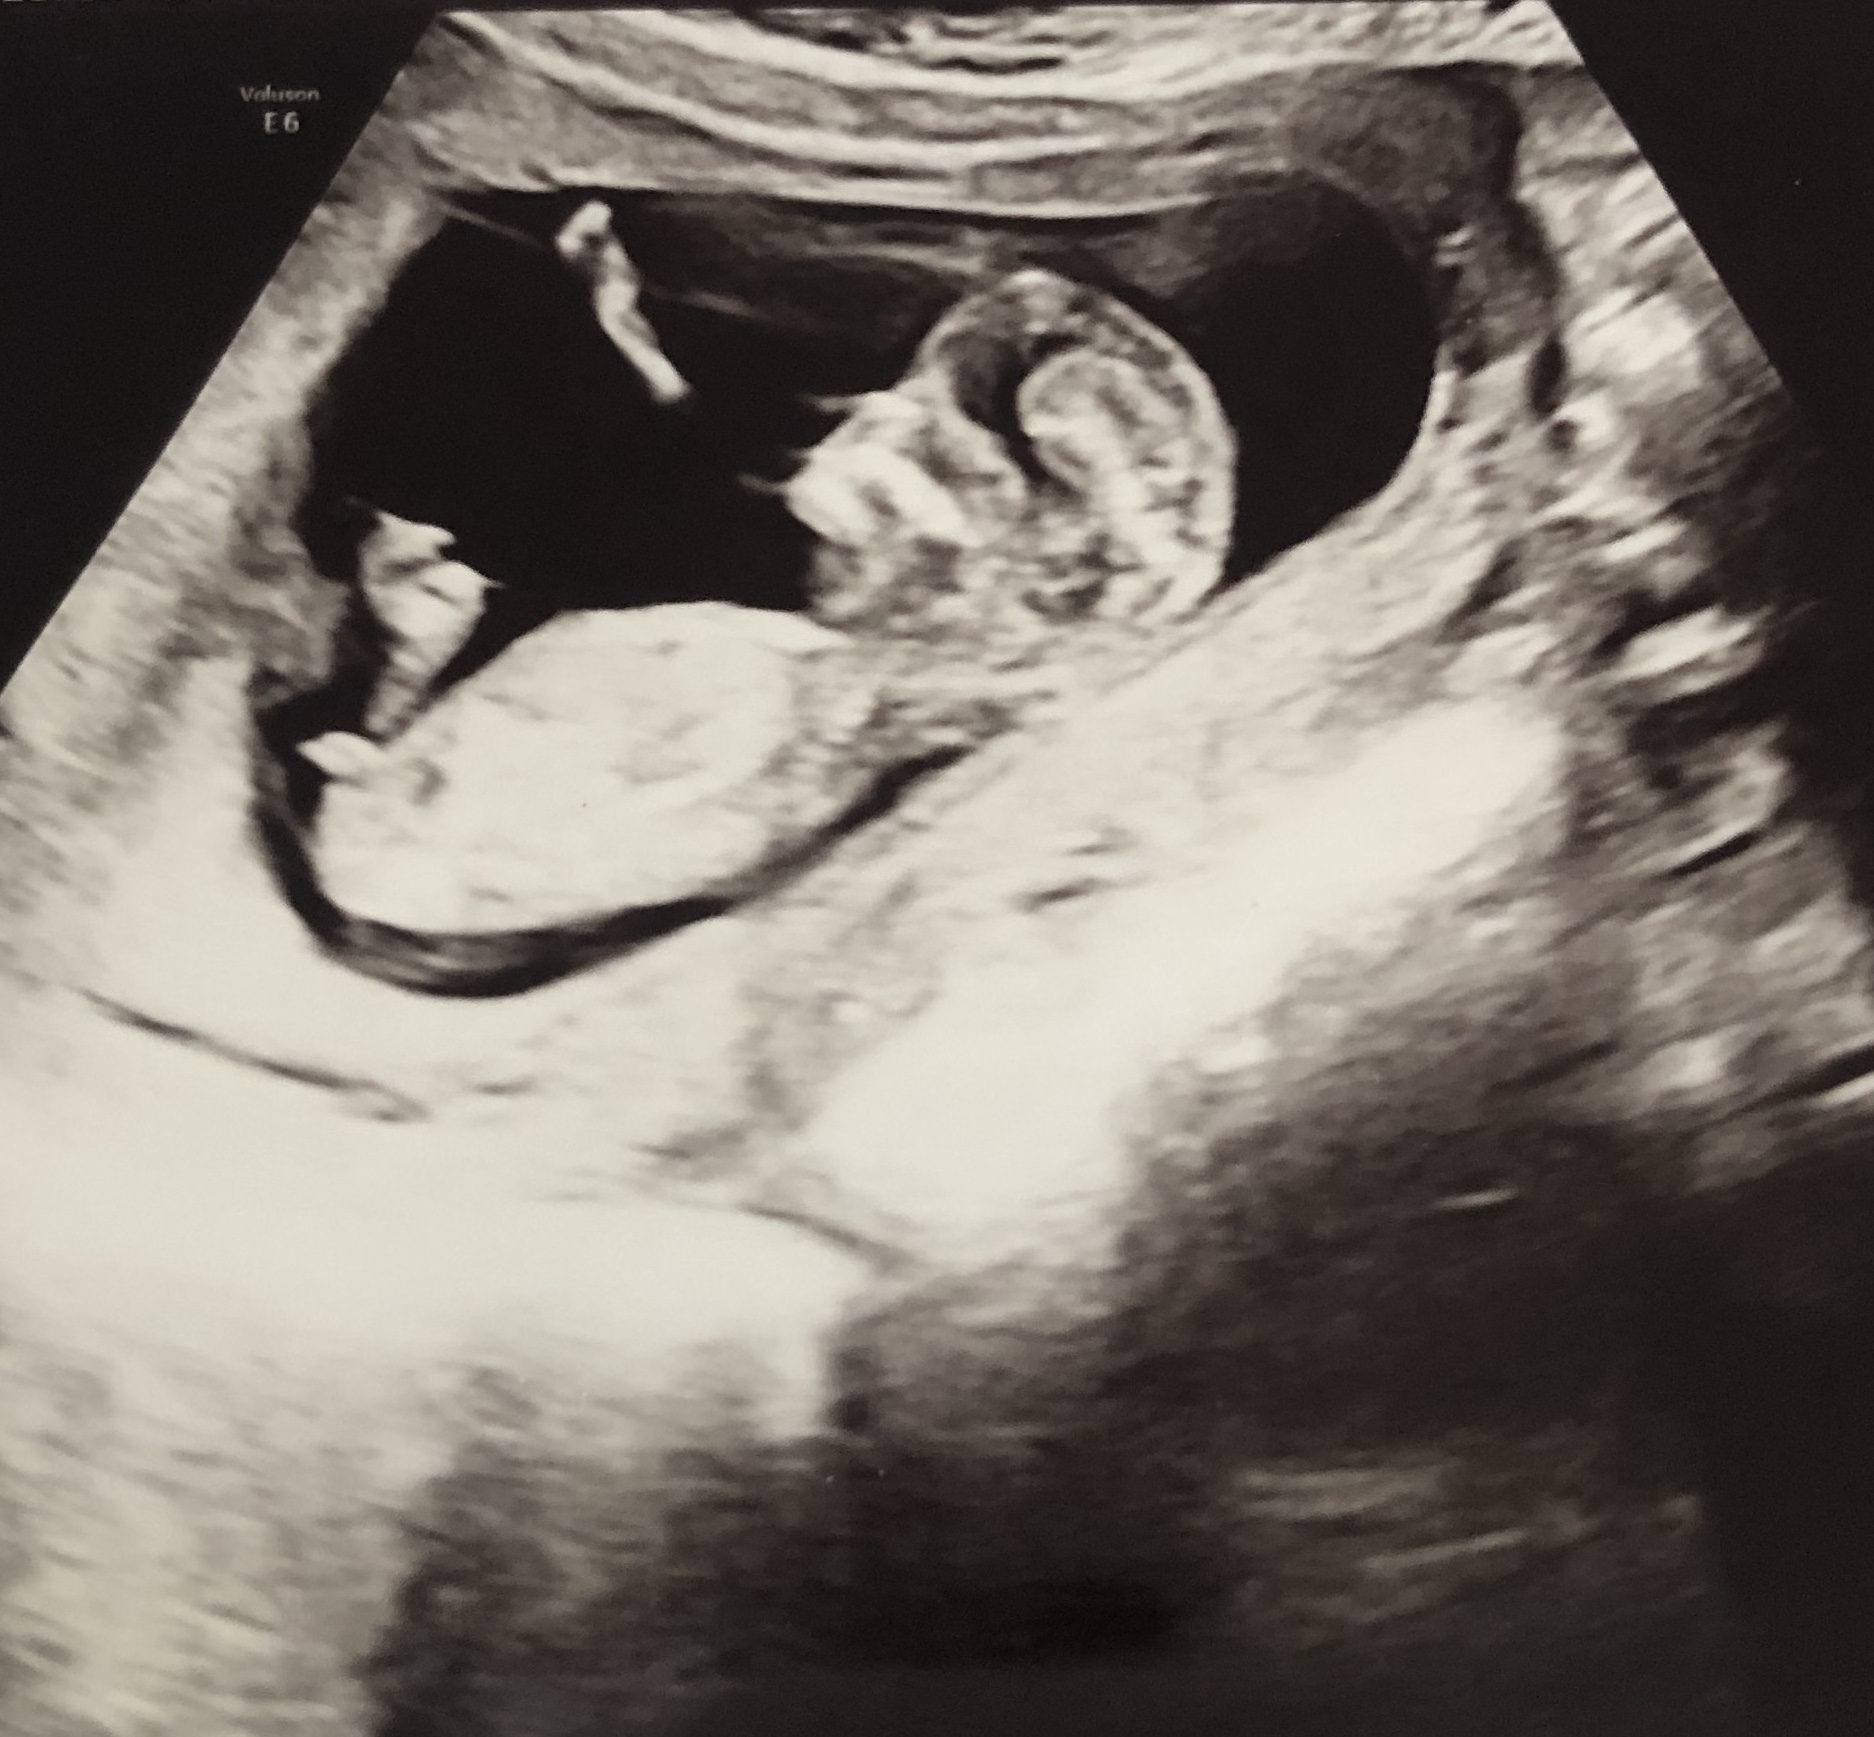

מבינות באולטסאונד? בן או בת..._shira_

מה הרופא אמר? אפילו לרופאים קשה להבחין באולטרסאונדבתי 123

אבל אין העובר לא מפסק_shira_

הרופא אמר שזה לא ברור אבל אולי בת

כן לחכות שיהיה בשעה טובהבתי 123

אף אחת פה לא תבין יותר טוב מרופאמיואשת******

כן. יש מלא טעויות בשלב הזה. חכי לסקירהאורוש3

אני רק-חולת שוקולד

אי אפשר לדעת מהתמונהבאורות

מה זה משנה העיקר בריאות בריאות בריאות 😍 איזה כיףanonimit48

זאת לא התנוחה הנכונה לבדוק מין עוברשירוש16אחרונה